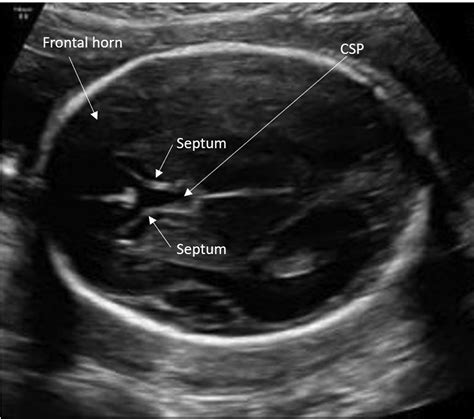

The Cavum Septi Pellucidi is a small, fluid-filled space located between the two leaflets of the septum pellucidum. The septum pellucidum is a thin, triangular, double membrane that separates the lateral ventricles of the brain. During normal fetal development, these two layers are separated by a space, which is the CSP.

The prevalence of a persistent CSP in the adult population is estimated to be between 1% and 3%, though some studies suggest it may be higher in certain demographics. Its appearance on imaging is distinct, typically appearing as a midline, fluid-filled structure that sits between the frontal horns of the lateral ventricles. Radiologists are well-trained to identify this feature and distinguish it from other, more concerning brain cysts or lesions.

It is common for patients to confuse the Cavum Septi Pellucidi with other similar-sounding structures. Understanding these differences helps in clarifying why a radiologist might report it as benign. The following table highlights common variations found in the midline of the brain:

Structure Description Clinical Significance

Cavum Septi Pellucidi Space between the septum pellucidum leaflets. Generally benign; incidental.